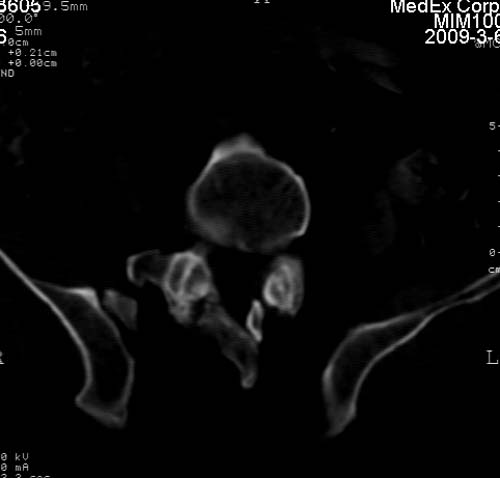

标题: CT18522:男,66岁。考虑结核有错吗 [打印本页]

标题: CT18522:男,66岁。考虑结核有错吗

x线片示:骶骨密度增高。

考虑----腰椎骶化-----退变-----椎管狭窄

腰骶椎退行性改变。

腰骶椎退行性改变,建议重建看看!

退行性变,椎体滑脱

腰椎滑脱并有退变

退行性变,椎体滑脱。建议同椎体平行进一步扫描。